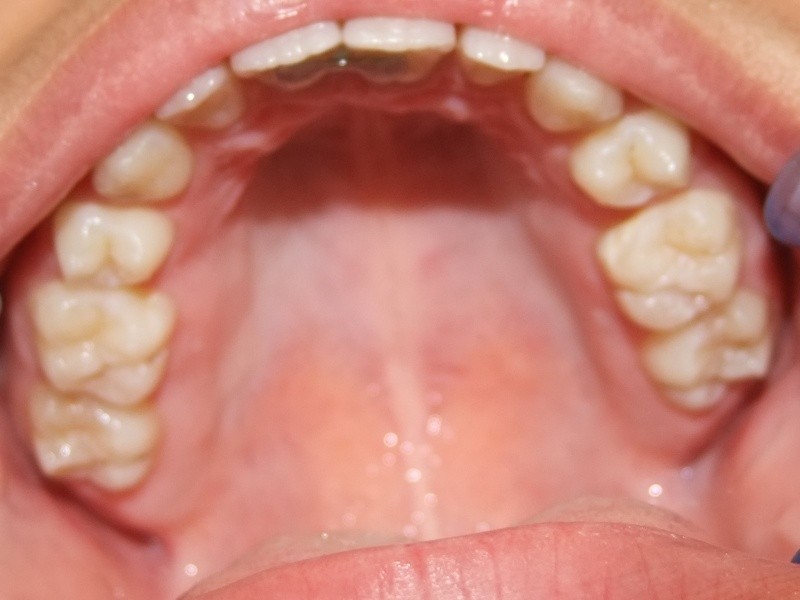

Behandeling Hajar

Beschrijving

Leeftijd bij aanvang: 9 jaar

1-6 maanden Bonded Hyrax in de bovenkaak, banden/slotjes in de onderkaak met Transforce

7-13 maanden: Twinblock

14-47 maanden: Volledig banden/slotjes in de boven-en onderkaak (omdat er hier blijvende kiezen ontbraken moesten er kiezen getrokken worden en de ontstane ruimtes gesloten, dit verklaart de langere behandeltijd)

Retentie fase: Wrap en C-CBar